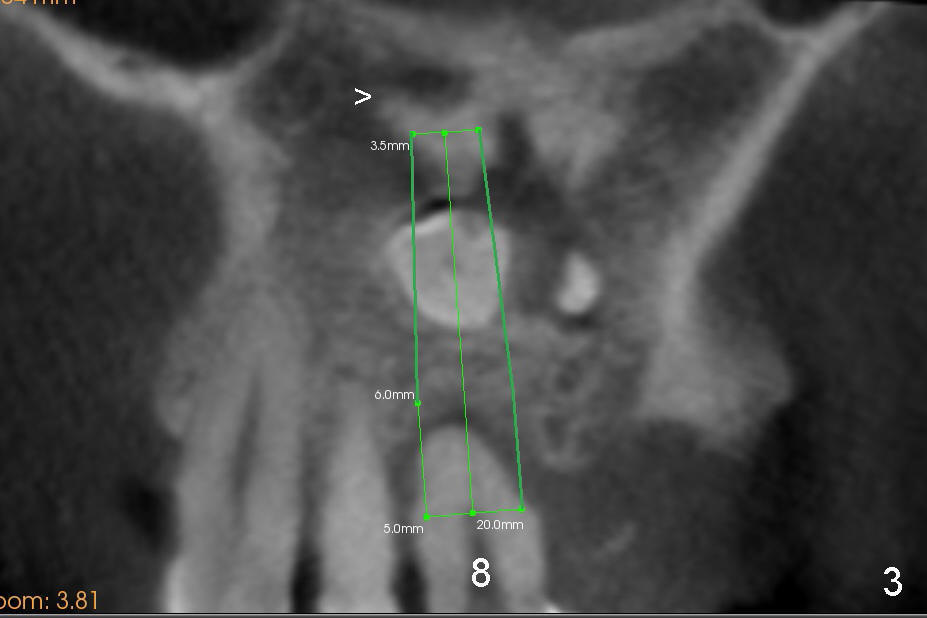

A 41-year-old man has poor dentition (Fig.1: #12 immediate provisional). It appears that #10 is congenitally missing. A temporary bridge is fabricated (Fig.1: #8-11) when #9 is reportedly extracted. Recently bonding between #9 pontic and #11 detaches. The bridge is loose (Fig.2). The tooth #8 is periodontally compromised (Fig.3,5: CT sagittal and coronal sections, respectively).

Treatment plan is to extract two supernumerary teeth (S1,S2) and #8, bone graft (mainly S1,2 sockets, and #8 buccal for cosmetics) and place immediate implants at the sites of #8 and 9. Long implants (20 mm) are to be used to engage into the two bone segments, coronal and apical to the S1,2 sockets (Fig.5,6). Since the bone segment apical S1,2 sockets is mainly cortical (arrowheads in Fig.3-6; lamina dura and nasopalatine canal), the two implants are expected to be stable. A palatal incision is going to be made to expose S1,2, as one of them (S2) is more or less palatal (Fig.6). Here is surgery.